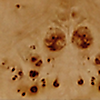

Complemented by clean lines and a minimal design, active burl wood veneer is the star of this 70-inch console table designed by VUUE. Thick rectangular legs stand flush with the top, providing structural interest without distracting from the wood's swirling grain. CB2 exclusive.

• Variation in burl wood is to be expected; each piece will be unique